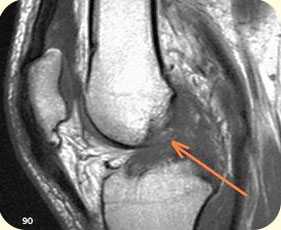

повреждение хряща и субхондрального слоя внутреннего мыщелка бедреной кости

2. ЯМРТ (ядерно-магнитно-резонансная томография) Современный, высокоинформативный, безопасный метод исследования. Лучше всего подходит для определения мягкотканых повреждений: связочного аппарата, повреждений менисков, хряща и др.

разрыв крестообразных связок коленного сустава (изображение слева), разрыв заднего рога внутреннего мениска коленного сустава (изображение справа)

1 - бедренная кость (наружный мыщелок);

2 - большеберцовая кость;

3 - задний рог латерального мениска;

4 - латеральная головка икроножной мышцы;

5 - суставная щель.